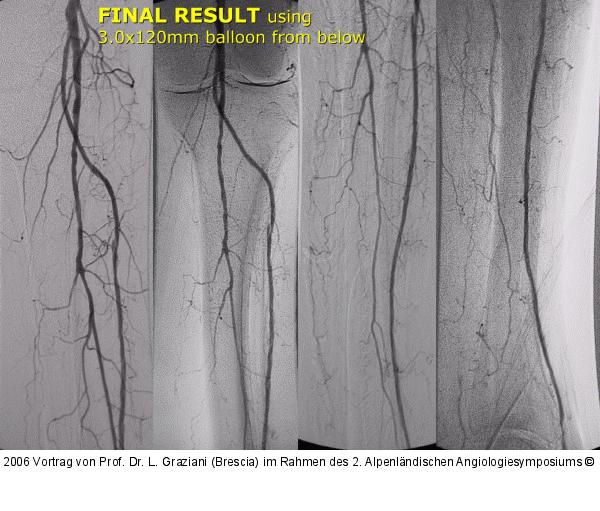

Vortrag von Prof. Dr. L. Graziani (Brescia) im Rahmen des 2. Alpenländischen Angiologiesymposiums

PTA of the foot arteries in diabetics: Extremities Extreme Angioplasty

Abbildung 72: Arteria dorsalis pedis - Katheterisation

Arteria dorsalis pedis - Katheterisation